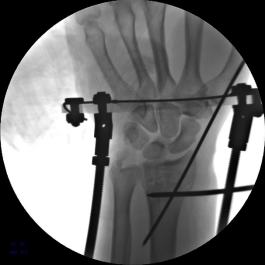

2.安装外固定架,调节螺母纵向牵拉,初步恢复桡骨高度

3.背侧穿针撬拨,继续恢复桡骨高度

7.手术完毕,复位满意